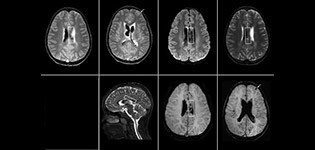

“SWIp helps us identify blood or blood products, calcification, and diseases that affect the vascular system,” says Dr. Miller. “In children with traumatic brain injuries, it highlights areas that are injured, better than some of the previous techniques that we were using. These children often have micro-injuries that cause small amounts of blood or tissue damage. Adding SWIp helps us to better characterize the extent and nature of the injury. Having characterized an injury to the extent of what’s possible supports our diagnostic confidence.”

“I would definitely recommend other users to implement SWIp. We initially added the SWIp sequence following a lot of support for its utility in the literature. Then we directly compared SWIp to the 2D gradient echo sequences that we were using. After a good amount of clinical experience in seeing its benefits, we were confident to replace the old sequences with SWIp. It gives us a better assessment of the physiological processes of the brain that were less apparent on our previous imaging sequences,” says Dr. Miller. “SWIp is now a routine sequence for imaging traumatic brain injury patients at PCH, and it’s episodically added for patients who have intracranial vascular abnormalities.”

“I believe SWIp is rapidly becoming the standard in imaging traumatic brain injury, because of its high sensitivity to venous blood products. SWIp may even help attract patients; our neurosurgeons often ask to have the patients imaged on our scanners with highly sensitive techniques like SWIp. There’s also a growing application of SWI sequences in other vascular abnormalities because of the possibilities around physiological assessment of the brain than just a standard structural imaging.”